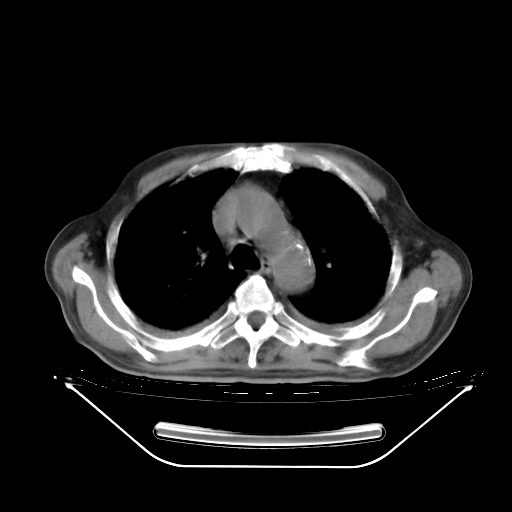

今天复查肺部CT,发现双肺广泛磨玻璃样改变。所以我把3月19日和5月9日相隔50天的肺部CT上传。请大家会诊。

2009年3月19日肺部CT片。

2009年3月19日肺部CT

胸腹部CT,诊断意见:左上肺叶钙化灶、左侧胸膜局限性增厚并钙化、胆囊炎。描述部分肺组织呈磨玻璃样改变。